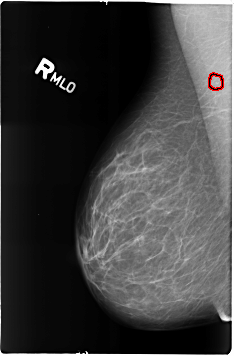

B_3165_1.RIGHT_MLO

FILE: B_3165_1.RIGHT_MLO.OVERLAY

TOTAL_ABNORMALITIES 1

ABNORMALITY 1

LESION_TYPE CALCIFICATION TYPE LUCENT_CENTER DISTRIBUTION N/A

ASSESSMENT 2

SUBTLETY 3

PATHOLOGY BENIGN_WITHOUT_CALLBACK

TOTAL_OUTLINES 1

BOUNDARY